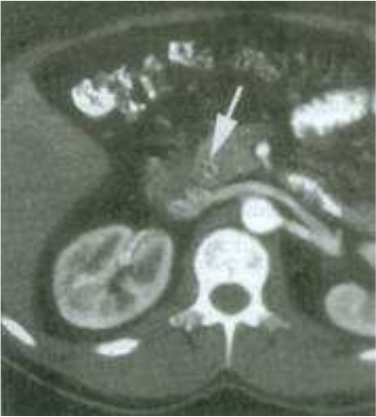

25.60歲女性因急性腹痛、發燒至急診處,血液檢查結果為bilirubin(total/direct):3.5/2.0 mg/dL,AST:100 U/L,ALT:75 U/L,腹部電腦斷層結果如圖,最可能的診斷為:

(A)急性肝炎 (B)急性盲腸炎 (C)急性膽管炎 (D)急性腸胃炎